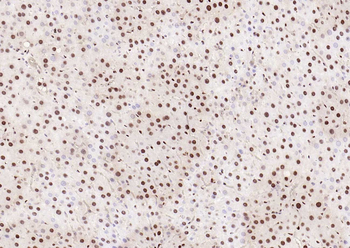

Phospho-Smad3 (Ser423 + Ser425) Rabbit Polyclonal Antibody [orb6983]

FC, IF, IHC-Fr, IHC-P, WB

Bovine, Canine, Equine, Gallus

Human, Mouse, Porcine, Rat

Rabbit

Polyclonal

Unconjugated

100 μl, 200 μl, 50 μlPhospho-SMAD5 (Ser463 + Ser465) Recombinant Rabbit Monoclonal Antibody [orb559123]